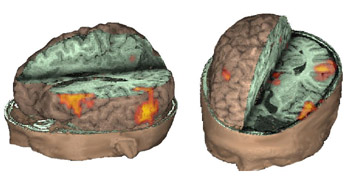

Case 2

Left lateral view and Top-posterior-left angled view.

Right handed 11 year-old-girl with intractable epilepsy who had a left frontal resection two years ago for control of seizures. Persistence of the seizures prompted this fMR exam for re-evaluation. The images demonstrated activation obtained from a "Verb Generation Task." The study depicted Broca's area and part of Wernicke's (Brodmann's area 37), which is believed to be a repository for words. A second resection was performed based on these findings. The patient experienced no post-operative aphasia and remains seizure free.